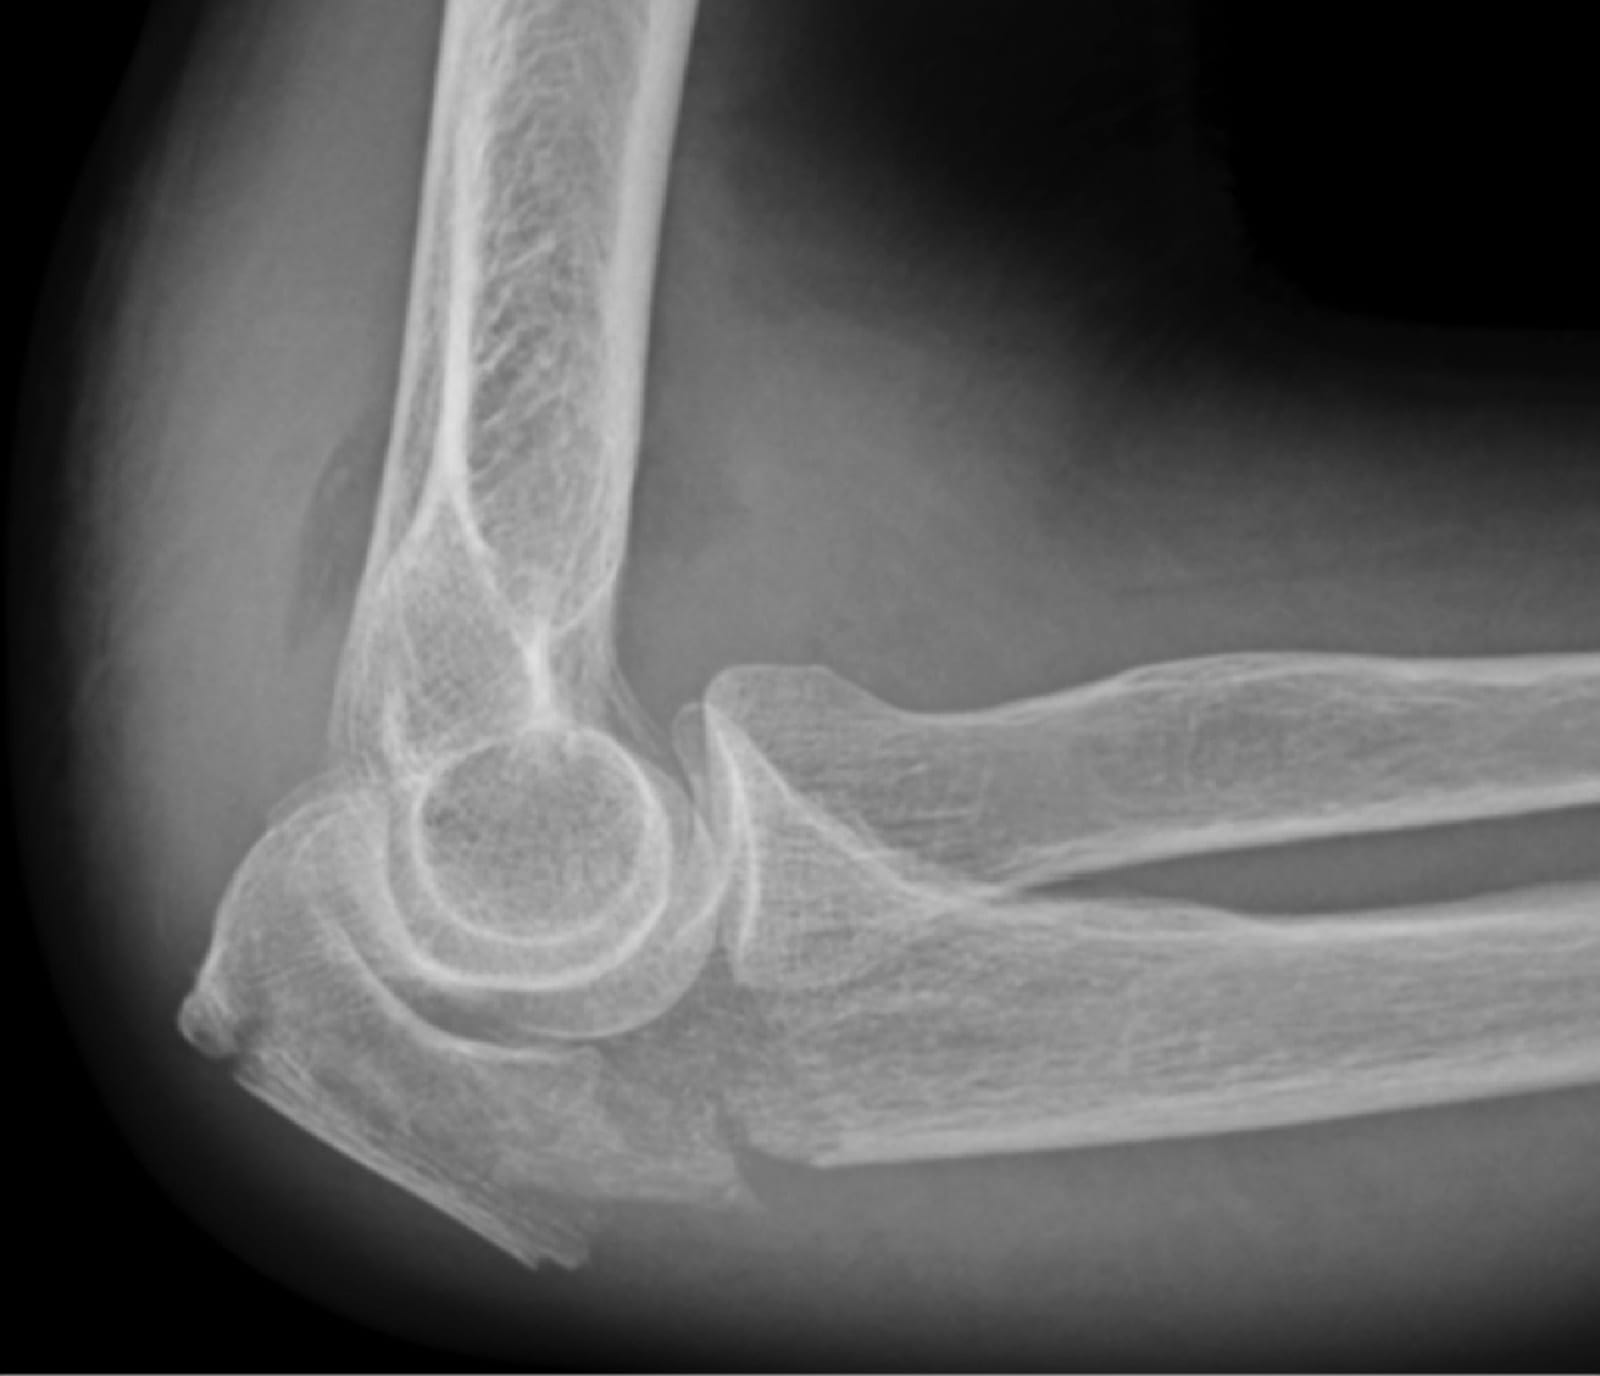

Luxación de codo AP: Ciertos accidentes pueden ocasionarnos que el codo se “safe” esto consiste en la dislocación o luxación del húmero distal del olécranon y de la cúpula radial. En esta radiografía vemos como se observa desde frente la lesión, y en la siguiente →

Luxación de codo LATERAL: observamos cómo se diagnóstica la luxación de codo en una radiografía desde perfil.